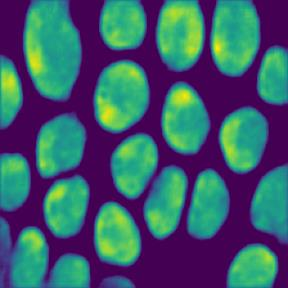

Microscopic image segmentation is a challenging task, wherein the objective is to assign semantic labels to each pixel in a given microscopic image. While convolutional neural networks (CNNs) form the foundation of many existing frameworks, they often struggle to explicitly capture long-range dependencies. Although transformers were initially devised to address this issue using self-attention, it has been proven that both local and global features are crucial for addressing diverse challenges in microscopic images, including variations in shape, size, appearance, and target region density. In this paper, we introduce SA2-Net, an attention-guided method that leverages multi-scale feature learning to effectively handle diverse structures within microscopic images. Specifically, we propose scale-aware attention (SA2) module designed to capture inherent variations in scales and shapes of microscopic regions, such as cells, for accurate segmentation. This module incorporates local attention at each level of multi-stage features, as well as global attention across multiple resolutions. Furthermore, we address the issue of blurred region boundaries (e.g., cell boundaries) by introducing a novel upsampling strategy called the Adaptive Up-Attention (AuA) module. This module enhances the discriminative ability for improved localization of microscopic regions using an explicit attention mechanism. Extensive experiments on five challenging datasets demonstrate the benefits of our SA2-Net model. Our source code is publicly available at \url{https://github.com/mustansarfiaz/SA2-Net}.